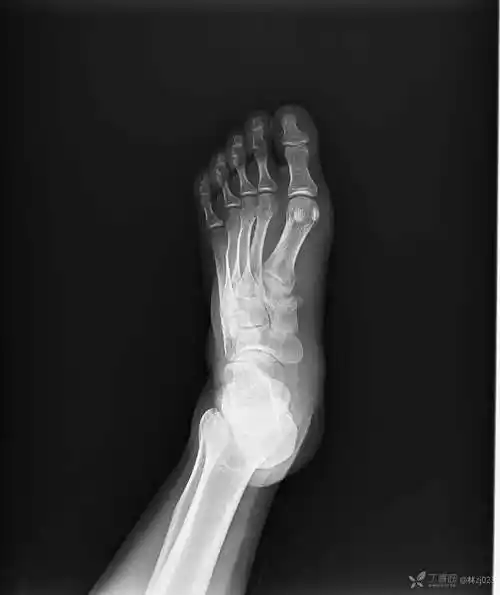

左足内侧楔骨见骨性突起